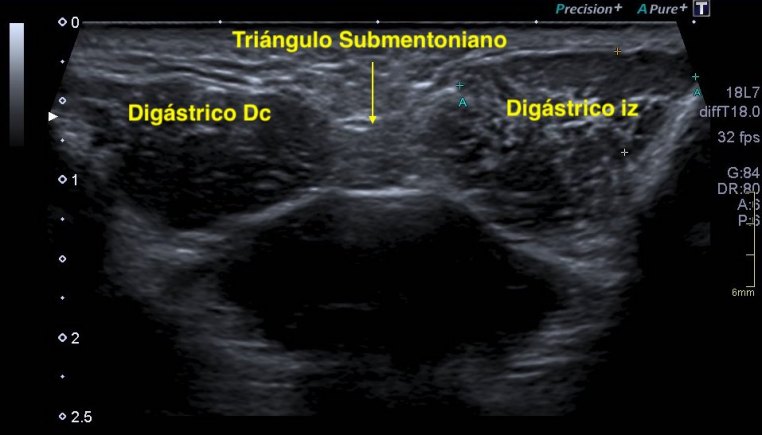

Los vientres anteriores de los Músculos Digástricos derecho e izquierdo forman los bordes laterales del triángulo submentoniano, mira:

En este triángulo lo que vas a encontrar son ganglios.